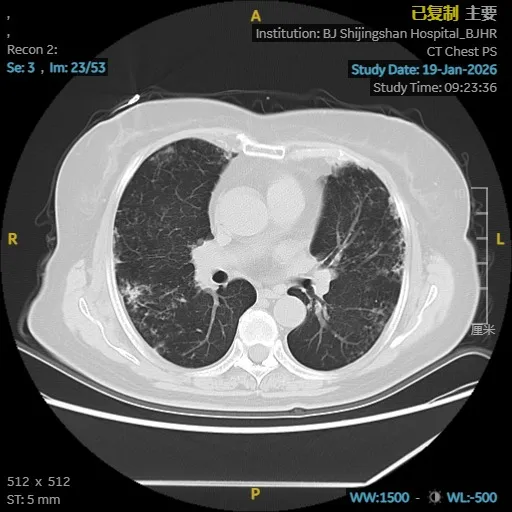

依托医院高清CT、肺功能、气管镜及精准分子检测平台,团队很快锁定了隐藏在表象背后的真实病因:鸟胞内分枝杆菌合并耐药念珠菌感染,同时伴有进展性肺间质纤维化。这两种疾病相互交织,诊治难度大,对医疗团队提出了很高要求。

为给患者制定最安全有效的治疗方案,马霞主任医师立即启动MDT机制,联合临床药师、影像科、检验科专家进行会诊。在多学科共同研判下,团队为栗女士量身定制了集抗感染、抗真菌、抗纤维化于一体的综合治疗策略,在精准打击病原的同时,全力保护肺功能。